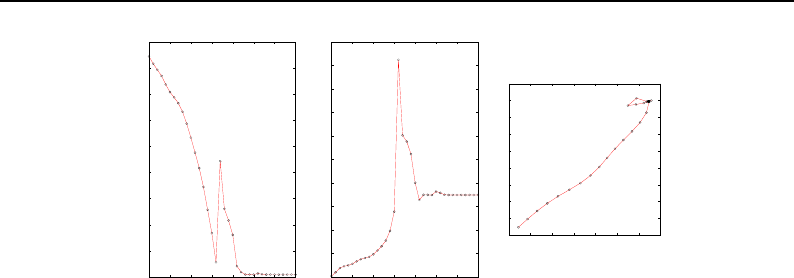

- Optimizers